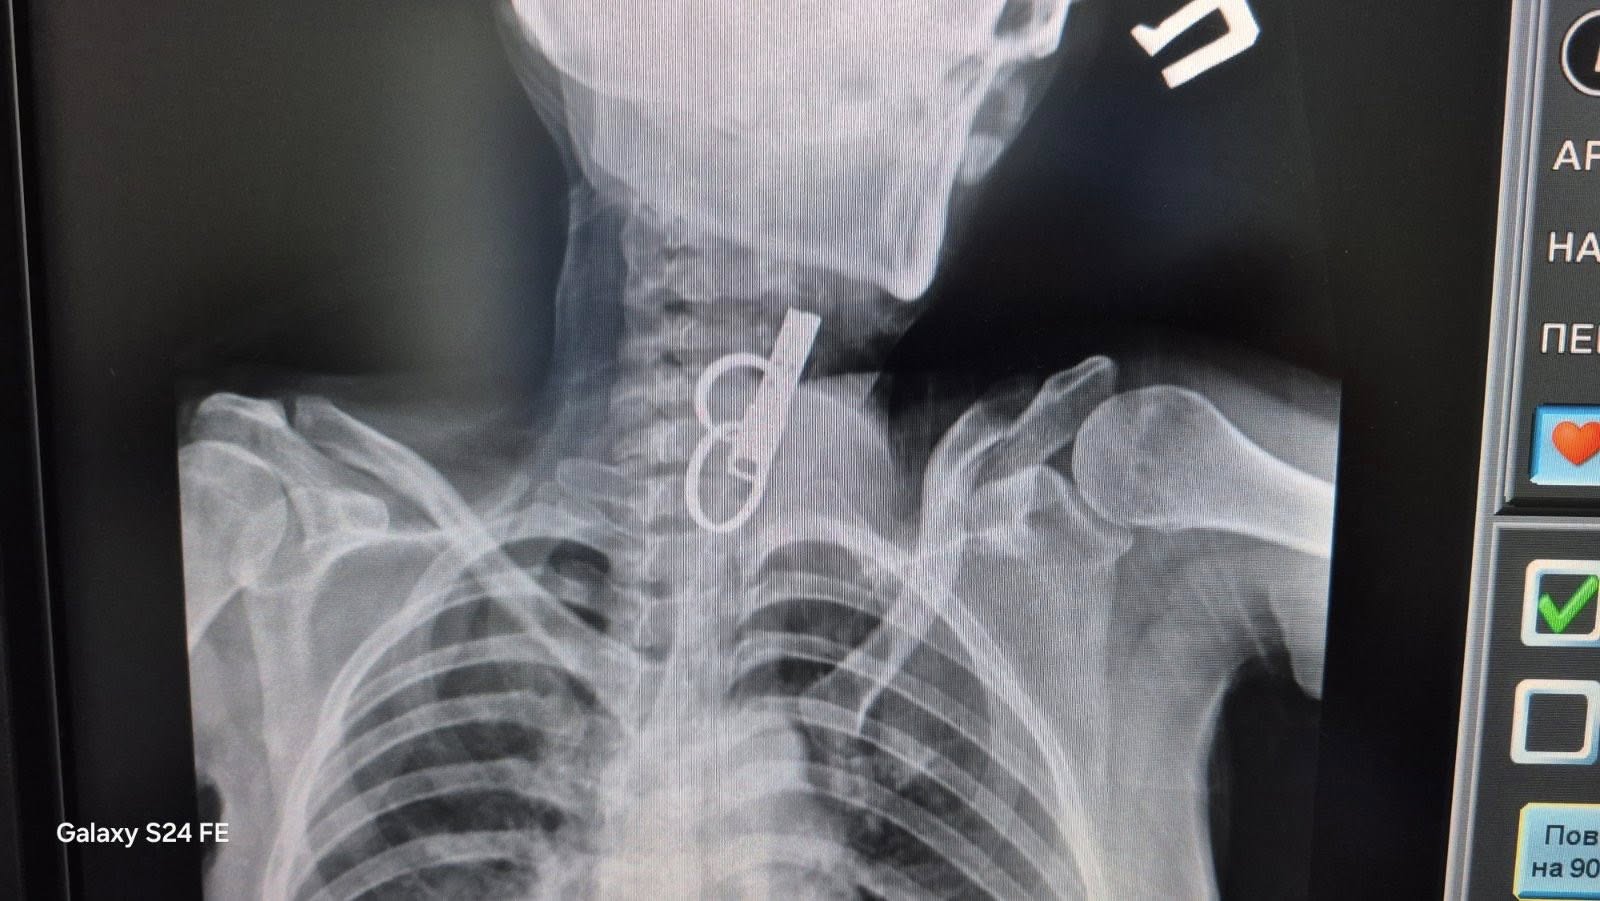

Про випадок повідомили у КНП «Гусятинська комунальна лікарня» Гусятинської селищної ради. Медикам вдалося без відкритої операції видалити зі стравоходу пацієнтки металевий ключ, який становив серйозну загрозу для життя.

У лікарні зазначають, що втручання провели ендоскопічним методом – завдяки сучасному обладнанню та злагодженій роботі медичної команди сторонній предмет дістали без хірургічного розрізу.

«Це один із тих випадків, коли рахунок іде на хвилини. Більшість пацієнтів із подібними ускладненнями не виживають. Спочатку ми бачили лише металеві кільця, а нижче – ще один невідомий предмет. Я припустив, що це може бути дверний ключ, і дуже обережно почав його витягувати», – пояснив лікар.